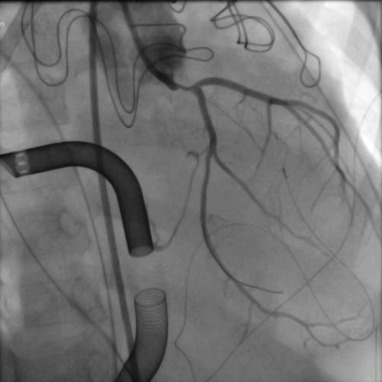

It was a pleasure presenting at #CRT2026 on valvular cardiogenic shock. @CRT_meeting I’m grateful for the mentorship and support from Drs. Hibbert, Thaden, and Simard.@MayoCVFellows @benhibbertMDPhD Mechanical problem → mechanical solution.

Rama Ellauzi tweet media